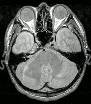

What type of image is it? MRI scans (T1 or T2 weighted)

Which plane the image is in? axial, sagittal or coronal (see

pictures below)

Saggital scan |